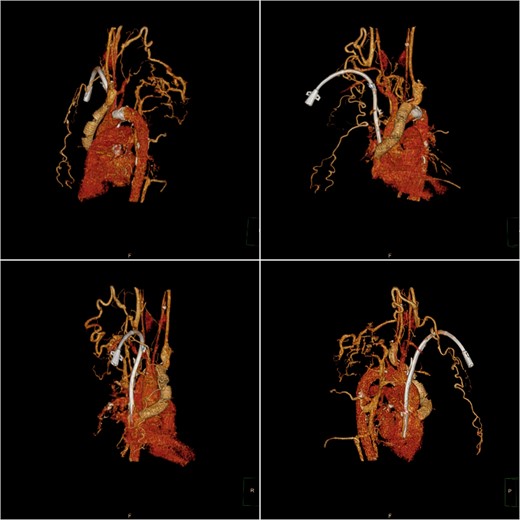

After a cardiac surgery consultation, the innominate-to-right-atrial bypass grafting technique under extracorporeal circulation and right atrial thrombus removal was planned. After anesthesia induction, the patient underwent central venous catheter placement in the left femoral vein as a route for anesthetic and vasoactive drugs. After the patient was fully heparinized, the sternum was opened for aortic cannulation and inferior vena cava drainage to establish extracorporeal circulation. During the operation, the right atrium was opened and a large calcified thrombus attached to the tunneled cuffed catheter was removed. Subsequently, the narrowed part of the unnamed vein was excised, and an artificial blood vessel (Gore R14030030L14mm*30 cm*30 cm) was anastomosed to the proximal end. After excising part of the right atrial appendage, the distal end of the artificial blood vessel was anastomosed to it, forming an innominate vein-to-right atrium artificial blood circulation (Fig. 1). The tracheal catheter was successfully removed after the operation. The patient currently has no symptoms such as arm swelling. The artificial blood vessel is unobstructed (Fig. 2), and normal dialysis is performed using the tunneled cuffed catheter.

Postoperative computed tomography angiography (CTA) showed no contrast agent leakage in the artificial blood vessel.

Postoperative computed tomography (CT) three-dimensional reconstruction shows the artificial blood vessel and tunneled cuffed catheter deformation.